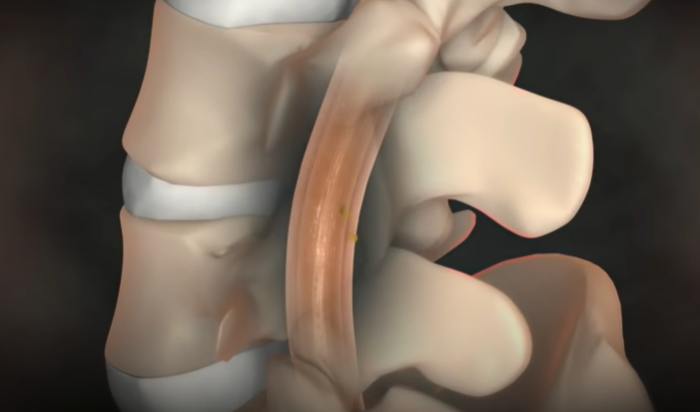

뇌척수액 누출로 인한 두통

뇌척수액이 척추 어디에선가 새어 빠져나가게 되면

그 위에 떠 있던 뇌가 아래로 주저앉으면서 심각한 두통을 유발한다.

물주머니에 뇌가 담겨 있다고 생각하면 된다. 물이 150cc 정도 있는데 그 안에 1.4kg 정도의 뇌가 떠 있다고 보면 된다. 이 무게를 실제 못 느끼는 것은 부력 때문인데, 물 주머니가 새는 경우가 있다. 그러면 물이 빠지면서 부력이 없어지니까, 뇌가 주저앉으면서 심한 두통을 일으킬 수 있는 것이다. 고통지수 10이라고 하면 10점 이상의 도통이라고 할 수 있다. 특징은 서있을 때는 척수액이 빠지기 때문에 굉장한 통증을 유발하는데, 누우면 최대 1분 내로 두통이 없어진다. 그러나 다시 일어나면 척수액이 더 빠지고 뇌가 밑으로 처지면서 극심한 통증이 재발한다.

뇌척수액 누출 두통의 치료

시술은 국소 마취제를 주사한 후에, 가느다란 관인 카테터를 척수를 싸고 있는 격막의 바깥 공간에 삽입하고

그 안으로 환자의 혈액을 주입하면 피가 응고되면서 누수를 막아 준다.

이때 새로 만들어진 뇌척수액이 채워지면서 주저앉았던 뇌가 제자리를 찾아간다.